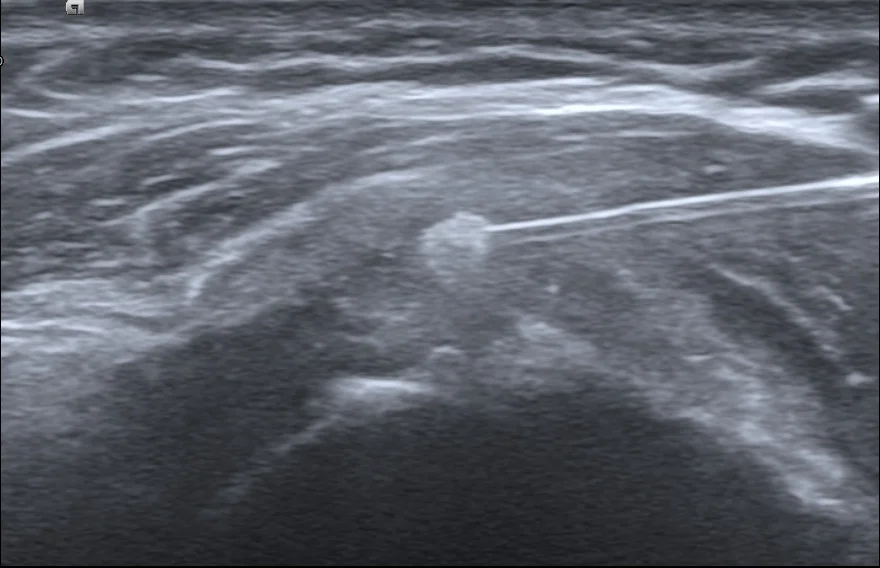

這項技術叫做「超音波導引鈣化沖洗術」 (Barbotage)。我們在即時超音波的監控下,將針頭精準地引導至鈣化中心,利用生理食鹽水反覆沖洗、抽吸。

治療過程中,螢幕上的畫面就像是挖掘工程。一開始那顆巨大的白色結石,隨著我們不斷地沖洗、抽出粉筆灰般的鈣化物,體積肉眼可見地開始縮小、崩解。患者看著螢幕,驚訝地說:「原來裡面真的有這麼多東西!」

到了治療尾聲,那顆原本巨大的「路障」,幾乎已經看不到了。